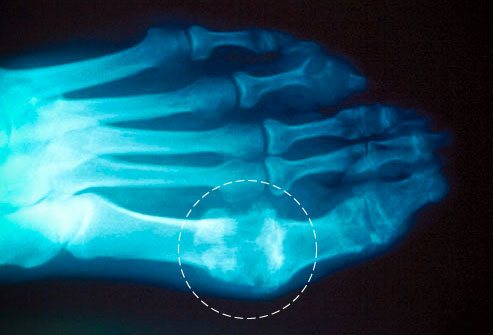

Рентгенография

На ранних стадиях заболевания метод рентгенографии не показывает характерных изменений в суставах.

Фото: подагра на снимке

При хронической форме подагры рентгенография определяет деструкции констнохрящевых зон:

- сужение суставных щелей из-за разрушения хряща;

- выраженные дефекты костных тканей;

- процесс эрозирования поверхности суставов;

- характерные уплотнения мягких тканей, которые окаймляют суставы;

- при вторичном остеоартрозе к перечисленным признакам добавляется краевой остеофитоз.

Самым типичным для подагры признаком является выраженный дефект костной ткани, образующийся в первом плюснефаланговом суставе и суставной зоне кистей.

Выделяют 3 типа рентгенографического исследования при хронической форме подагрического артрита:

- Исследование крупных кистов в субхондральной зоне

- Обследование крупных кистов, расположенных вблизи суставов, и мелких эрозий на поверхности суставов.

- Исследование больших эрозий, которые занимают 1/3 часть суставной поверхности.